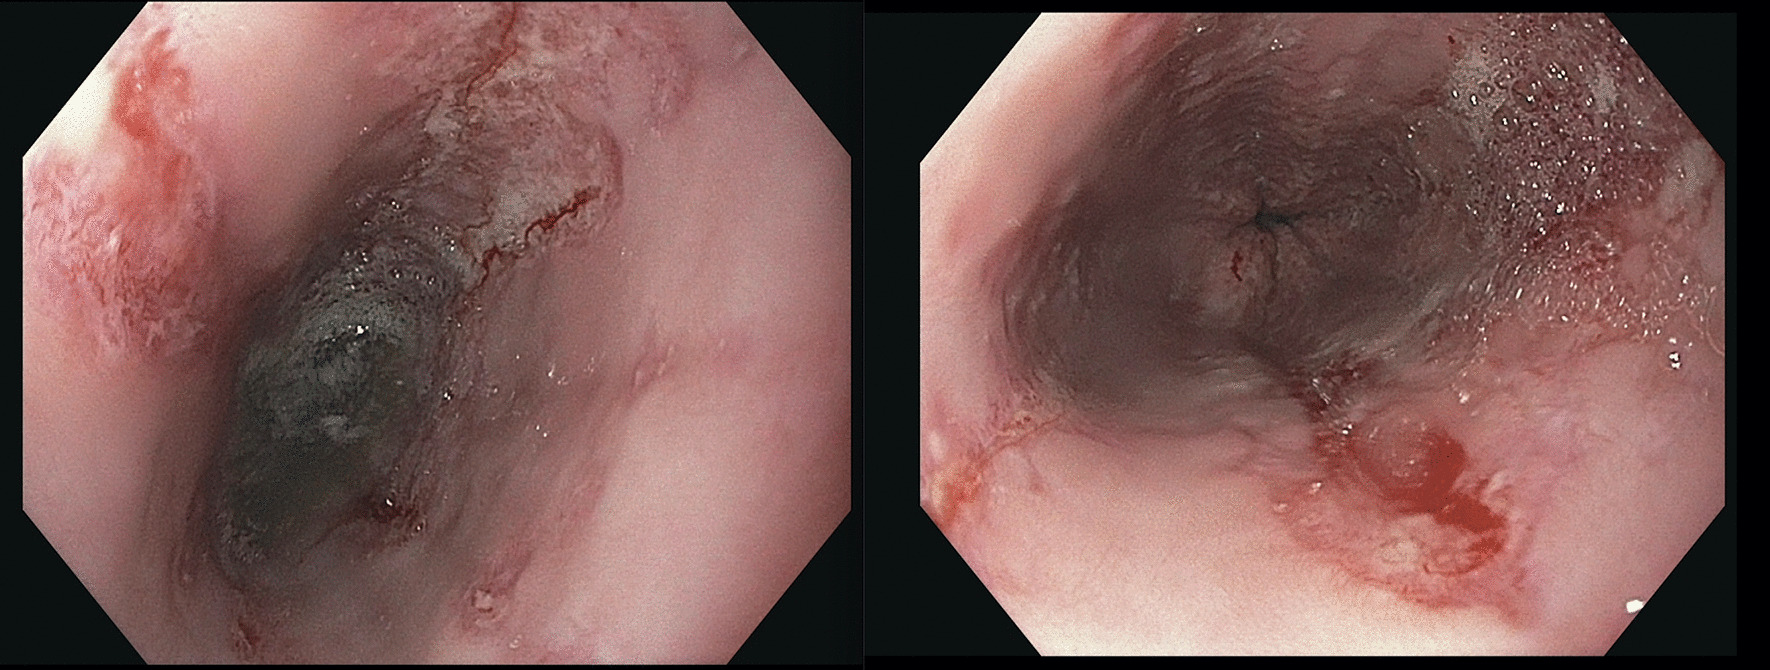

We performed esophagogastroduodenoscopy that revealed Los Angeles Grade C esophagitis (involving ≥ 1 mucosal breaks continuous between tops of ≥ 2 mucosal folds, < 75% circumferential) (Fig. 1). Histopathological analysis of esophageal biopsies demonstrated granulation tissue with acute and chronic inflammation (Fig. 2). Periodic acid-Schiff-diastase staining was negative and immunohistochemical stains for herpes simplex virus and cytomegalovirus were negative. There was no evidence of eosinophilic esophagitis. He was diagnosed with esophagitis secondary to vaping. We treated him with intravenous 40 mg twice daily PPI and analgesics until he was able to tolerate oral intake. He was counseled extensively on vaping cessation. The patient reported complete resolution of symptoms after 2 months of PPI therapy and vaping cessation.